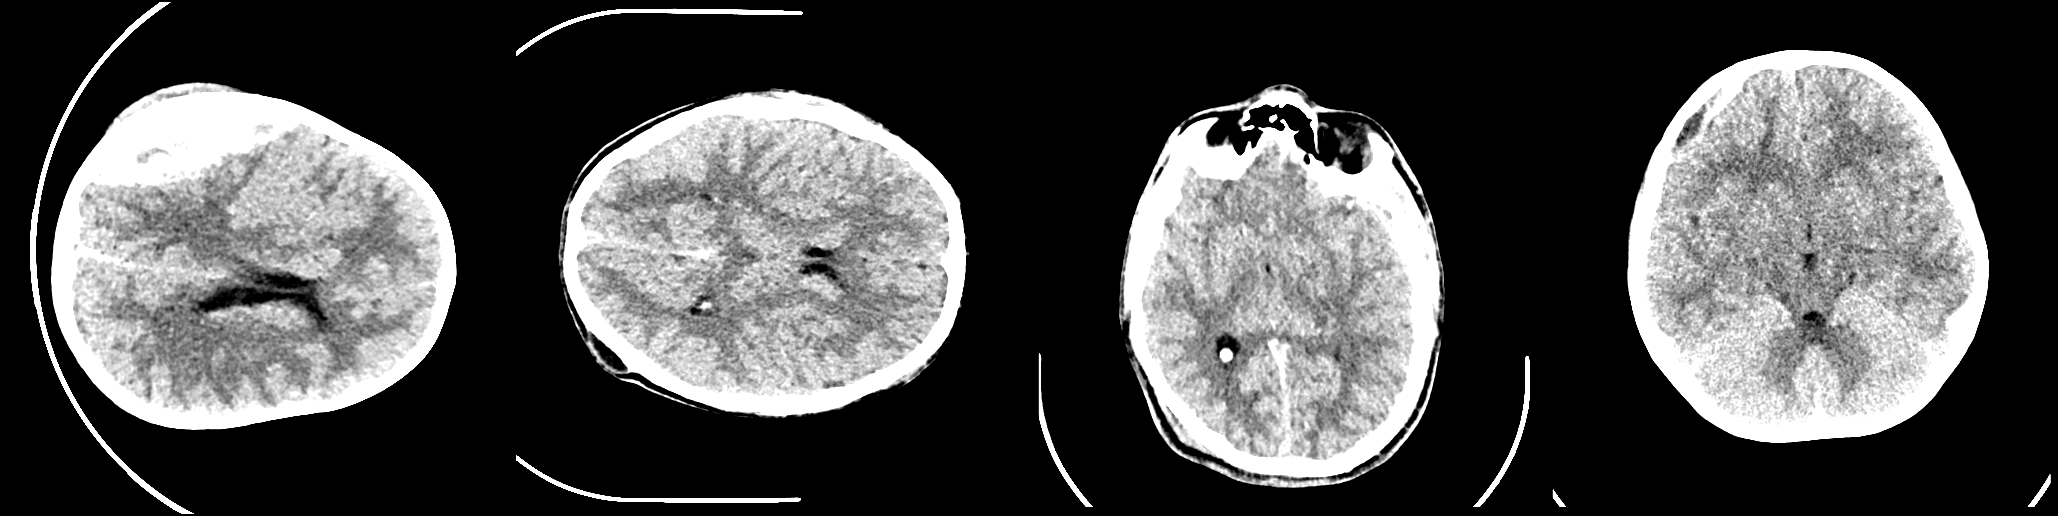

Haemorrhaging of the brain is the leading cause of death in people between the ages of 15 and 24 and the third leading cause of death in people older than that. Computed tomography (CT) is an imaging modality used to diagnose neurological emergencies, including stroke and traumatic brain injury. Recent advances in Deep Learning and Image Processing have utilised different modalities like CT scans to help automate the detection and segmentation of brain haemorrhage occurrences. In this paper, we propose a novel implementation of an architecture consisting of traditional Convolutional Neural Networks(CNN) along with Graph Neural Networks(GNN) to produce a holistic model for the task of brain haemorrhage segmentation.GNNs work on the principle of neighbourhood aggregation thus providing a reliable estimate of global structures present in images. GNNs work with few layers thus in turn requiring fewer parameters to work with. We were able to achieve a dice coefficient score of around 0.81 with limited data with our implementation.